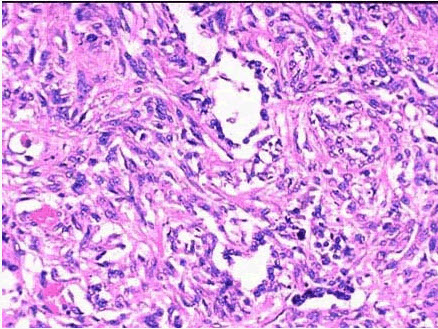

58、单项选择题

患者,女,23岁,咳嗽伴发热、食欲减退、体重减轻1年,X线检查显示双侧肺门及纵隔淋巴结对称肿大,行纤支镜活检。

镜下如图所示,正确的诊断是()

患者,男,70岁,慢性支气管炎伴阻塞性肺气肿20余年,加重一年伴心力衰竭而死亡,尸检见双肺体积增大,充气膨胀,表面见肋骨压痕。右心壁厚0.6cm,右心腔明显扩张,乳头肌及肉柱显著增粗,肺动脉圆锥膨隆,左心及各瓣膜未见明显病变。

肺组织镜检见间质中小动脉壁增厚纤维化(如图),综合所见,正确的诊断是()